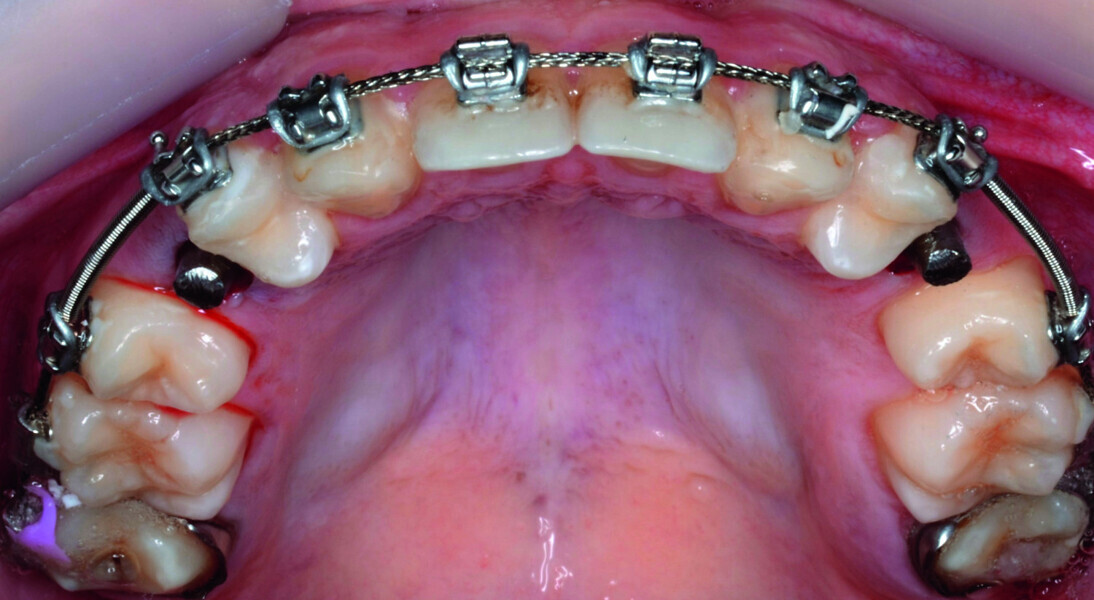

Orthodontic management of maxillary lateral incisors agenesis